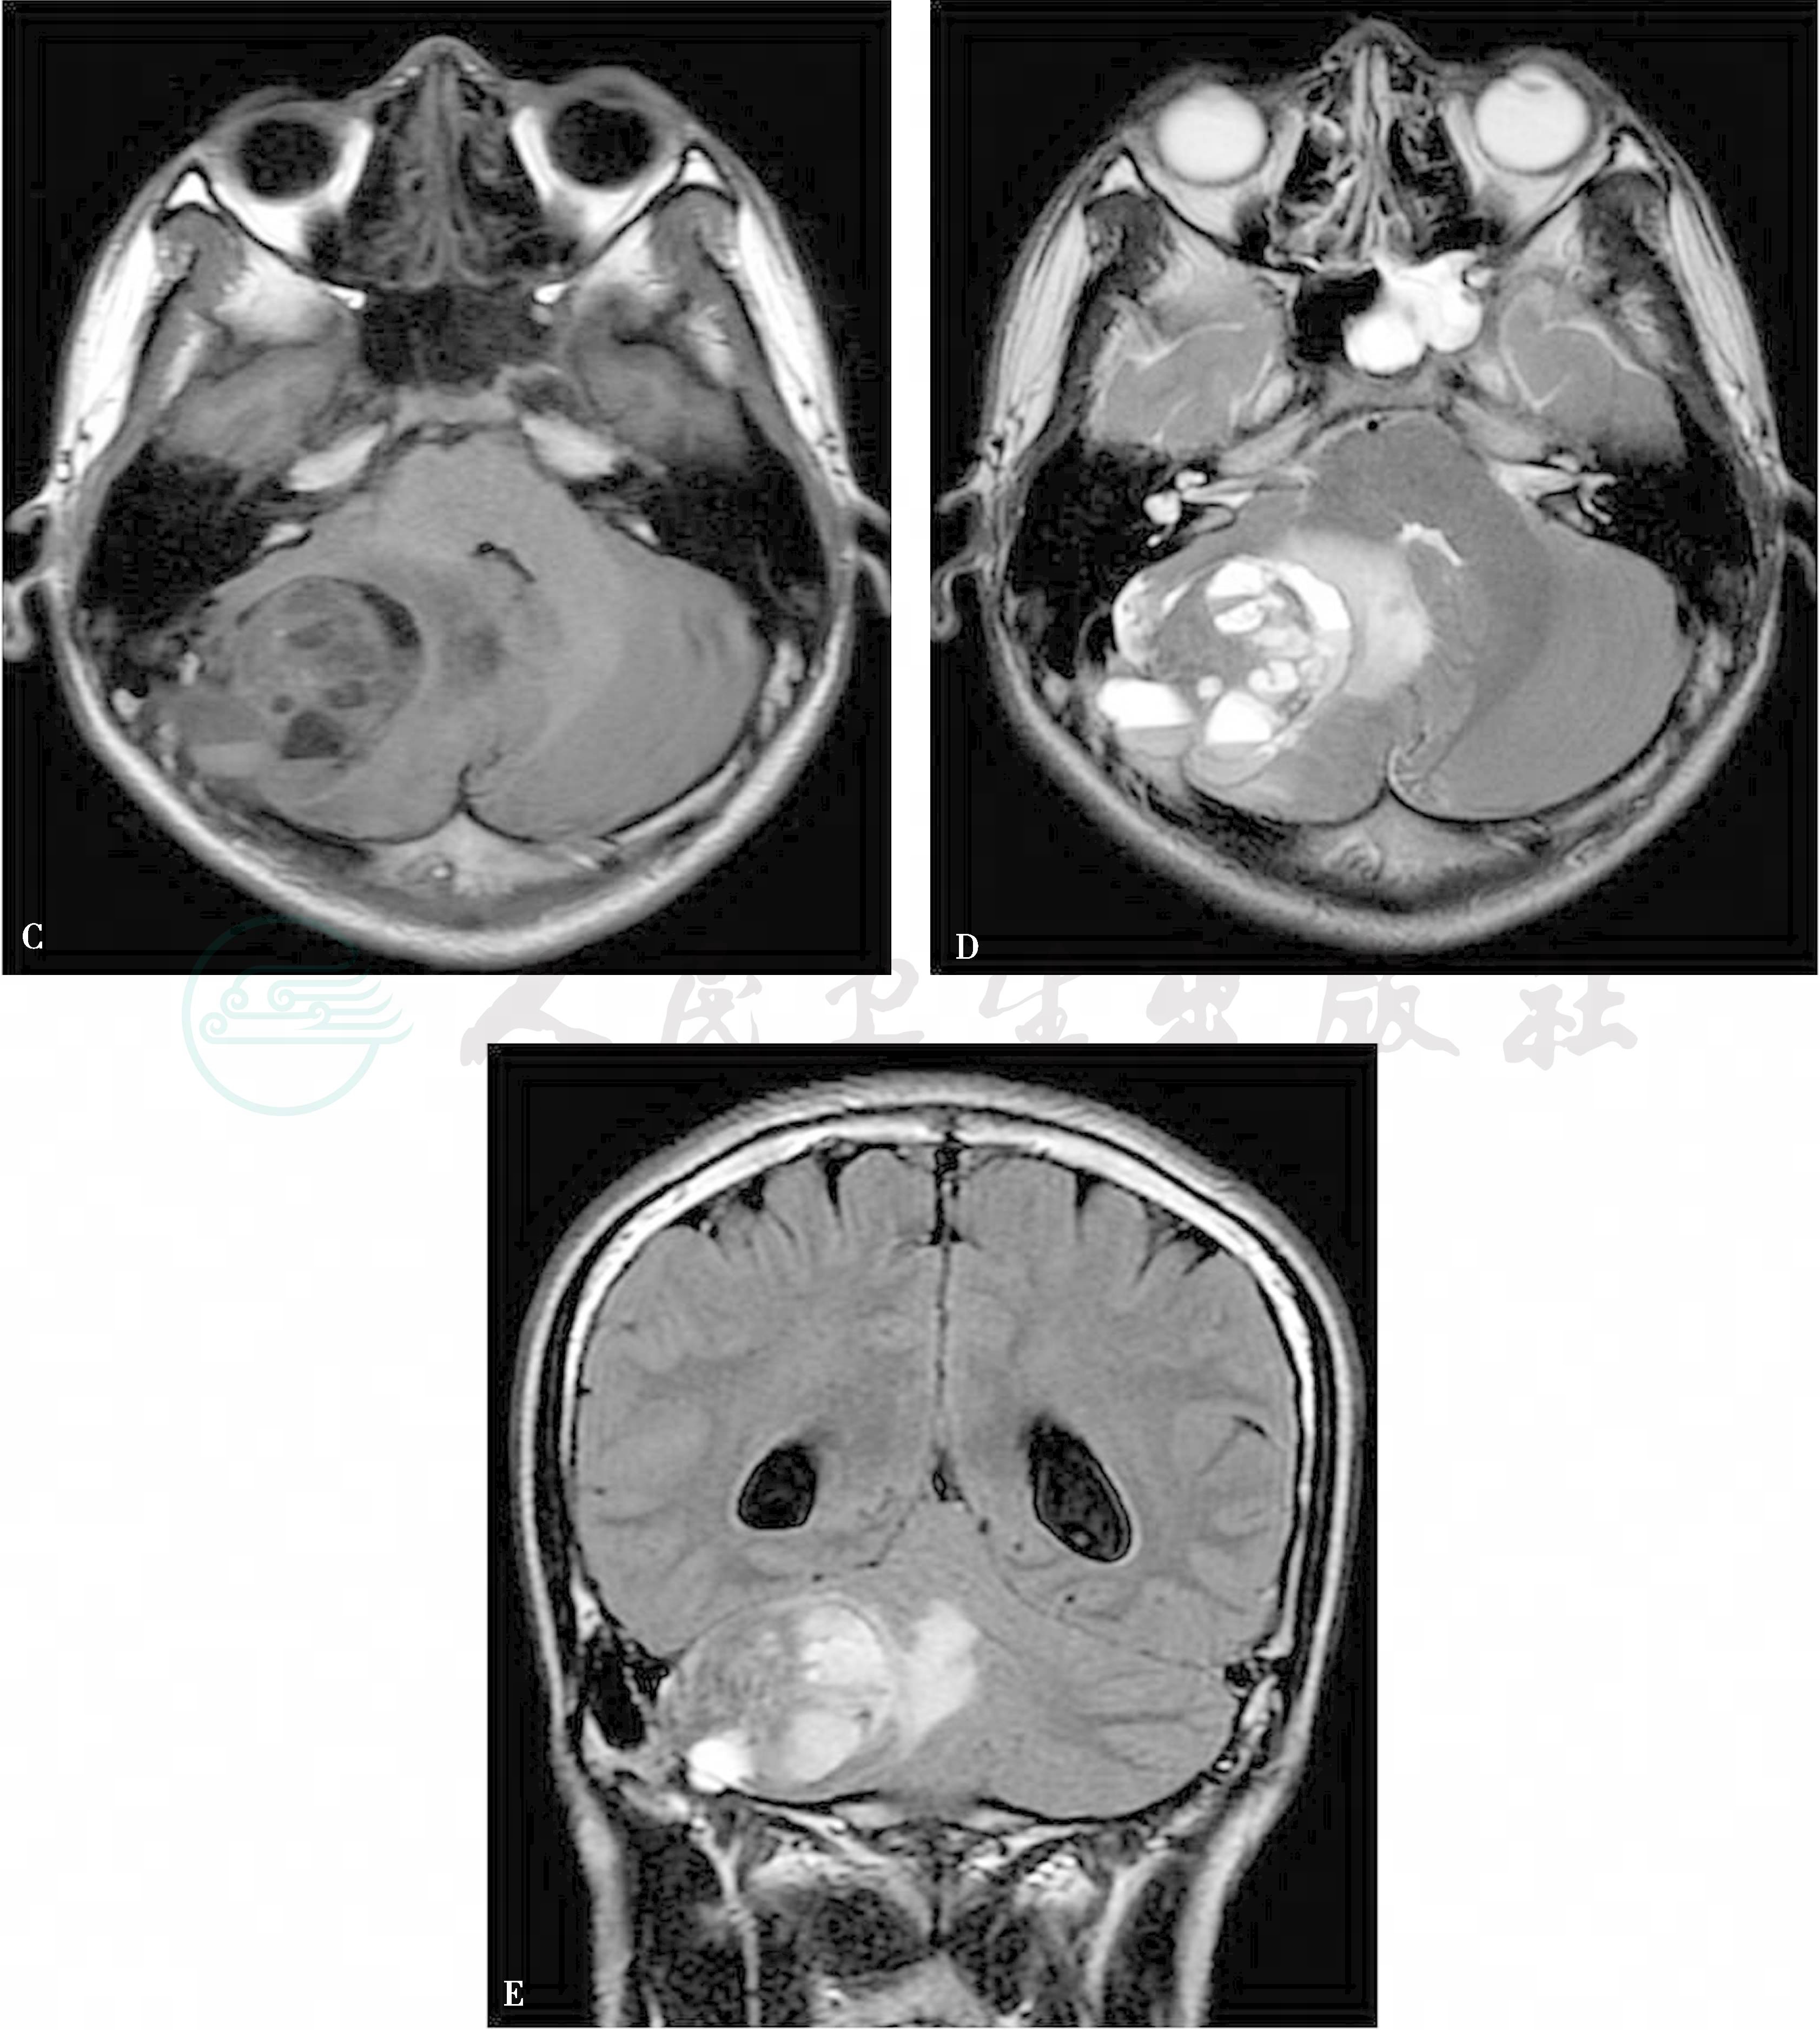

MRI表现 主要表现为边界清楚的多房分叶状囊性膨胀性骨破坏病灶,边缘有薄如纸的低信号边界,囊腔大小不一,信号不均,在T2WI上呈高信号,T1WI上呈等或低信号,部分可为高信号,多数患者可见典型的液-液平面,在T2WI上显示较清,特别是在TE较长的重T2WI上更为清楚。液面上部呈明显长T1长T2信号,下部多呈等T1等T2信号(图1C~E)。

图1 动脉瘤样囊肿

A、B:CT示右侧颞枕骨交界处见囊状膨胀性病变,边界清楚,局部颅骨内外板膨胀、消失,病灶向颅内延伸形成较大多房状略高密度肿块,内见多个液-液平面,邻近脑组织受压,周围见片状低密度水肿区;C~E:MR扫描显示右侧颞枕部见边界清楚的多囊状肿块影,呈等长T1、等长T2混杂信号,边缘有薄如纸的低信号边界,囊腔大小不一,信号不均,可见液-液平面,液面上部呈明显长T1长T2信号,下部呈等T1等T2信号,病灶周围见条片状长T1长T2水肿影